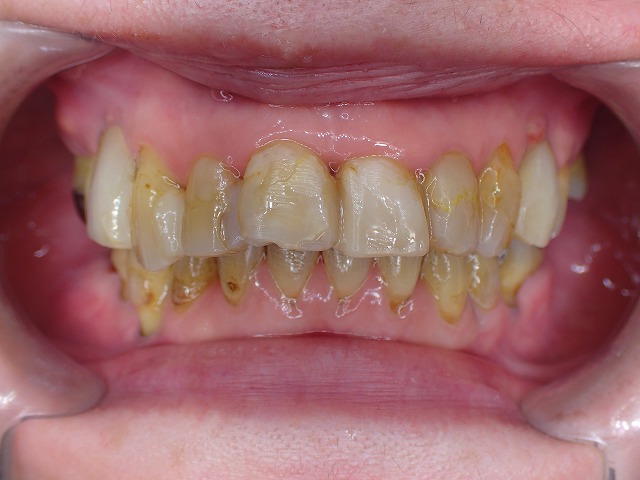

歯がグラグラでも、長期に歯を残す

歯周病で歯の固定

この状態でも歯を抜去せずに

10年以上維持しています。

歯周病固定 実例3 歯を抜きたくないと15年以上 長期の観察管理・予防処置

末期中の末期 この状態でも15年以上維持できている

大切なのはご本人の自由意志

最後まで持たせたいという患者さんのご希望

コンポジットレジン充填の際に

それを連結することで、固定。

もっとも重要なことは歯肉の炎症に対する

歯周病処置 予防処置です。

咬み合わせのバランスにより、歯が移動しているので

左右が非対称です。

半分開口した状態です。